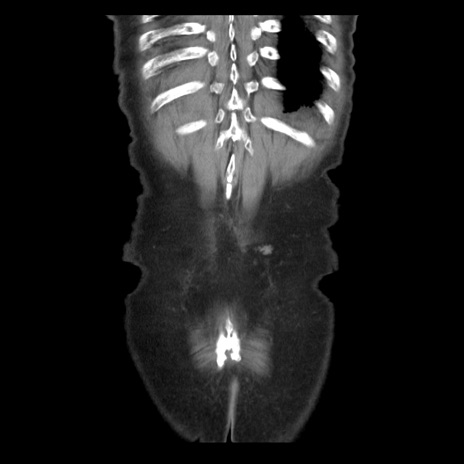

症例21(冠状断像)

【症例】70歳代男性

【主訴】腹痛

【現病歴】肝硬変・肝細胞癌にてかかりつけの方。約9時間前に食後より腹痛出現。症状が徐々に増悪し、嘔吐出現したため来院。

【既往歴】肝硬変、肝細胞癌(RFA、TACE後)

【身体所見】意識清明、表情苦悶様、BT 36℃、BP 129/78mmHg、P 88bpm、SpO2 97%(RA)、右上腹部から心窩部にかけて圧痛あり、反跳痛なし、筋性防御あり。

【データ】WBC 5800、CRP 0.16